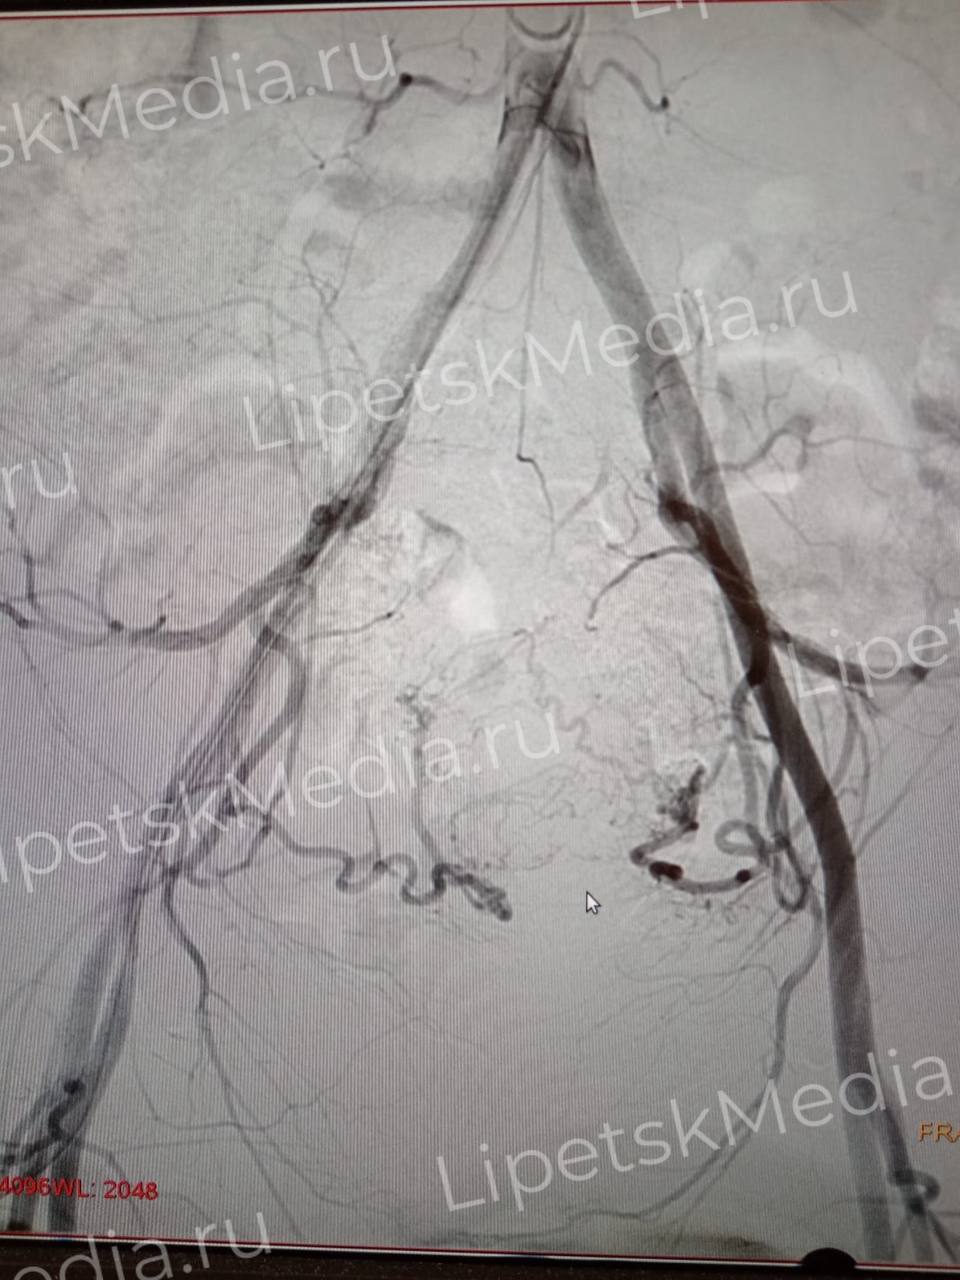

После тщательного обследования им выполнили эндоваскулярные операции по эмболизации маточных артерий.

Во время вмешательства в кровоснабжающие сосуды миомы матки вводят эмбосферы. Они перекрывают просвет сосуда, опухоль перестает расти, а в дальнейшем уменьшается в размерах, сообщают медики.